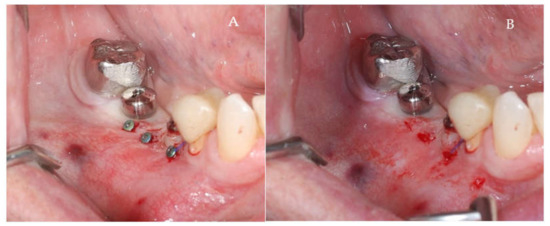

Clinical and CBCT aspects of patient from the test group, describing the stages of S-GBR technique and implant-prosthetic stage, are presented in Figure 1, Figure 2, Figure 3, Figure 4, Figure 5, Figure 6, Figure 7, Figure 8, Figure 9, Figure 10 and Figure 11. CBCT exam allows the evaluation of the horizontal alveolar bone defect and the position of the mandibular alveolar nerf (Figure 1A,B). Figure 1C,D show cross-sectional CBCT aspects of the implant sites. Figure 2 shows the narrowed mandibular alveolar bone with horizontal resorption. Figure 3 shows the exposed buccal surface of the alveolar ridge with severe horizontal resorption, after flap opening. The inserted implants (4.5 mm diameter, 11.5 mm length) and osteosynthesis screws (45° from the occlusal plan) are shown in Figure 4A. The placement of graft (autologous bone and xenograft) and collagen membrane is shown in Figure 4B. Figure 5A shows tension-free sutures, due to periosteal incisions alveolar ridge. Figure 5B shows clinical aspect at 7 months after surgery, with gingival tissue adherent on the reconstructed alveolar ridge. Figure 6 shows OPG aspect at follow-up of 7 months, with osseointegration of the dental implants. Figure 7A shows clinical aspect before osteosynthesis screws removal. Figure 7B shows clinical aspect after osteosynthesis screws removal. Figure 8A shows healthy peri-implant soft tissues. Figure 8B shows repositioning key for perfect position of abutments. Figure 10A,B show clinical aspects of implant-supported prosthetic restoration. Figure 11A,B show CBCT aspects of Osseo integrated dental implants at 24 months follow-up.

Figure 4.

(A,B) Intra-operative clinical aspects. (A) Clinical aspect of the inserted implants and osteosynthesis screws. (B) Clinical aspect of the graft material and collagen membrane placed to delimit the future bone regeneration compartment.